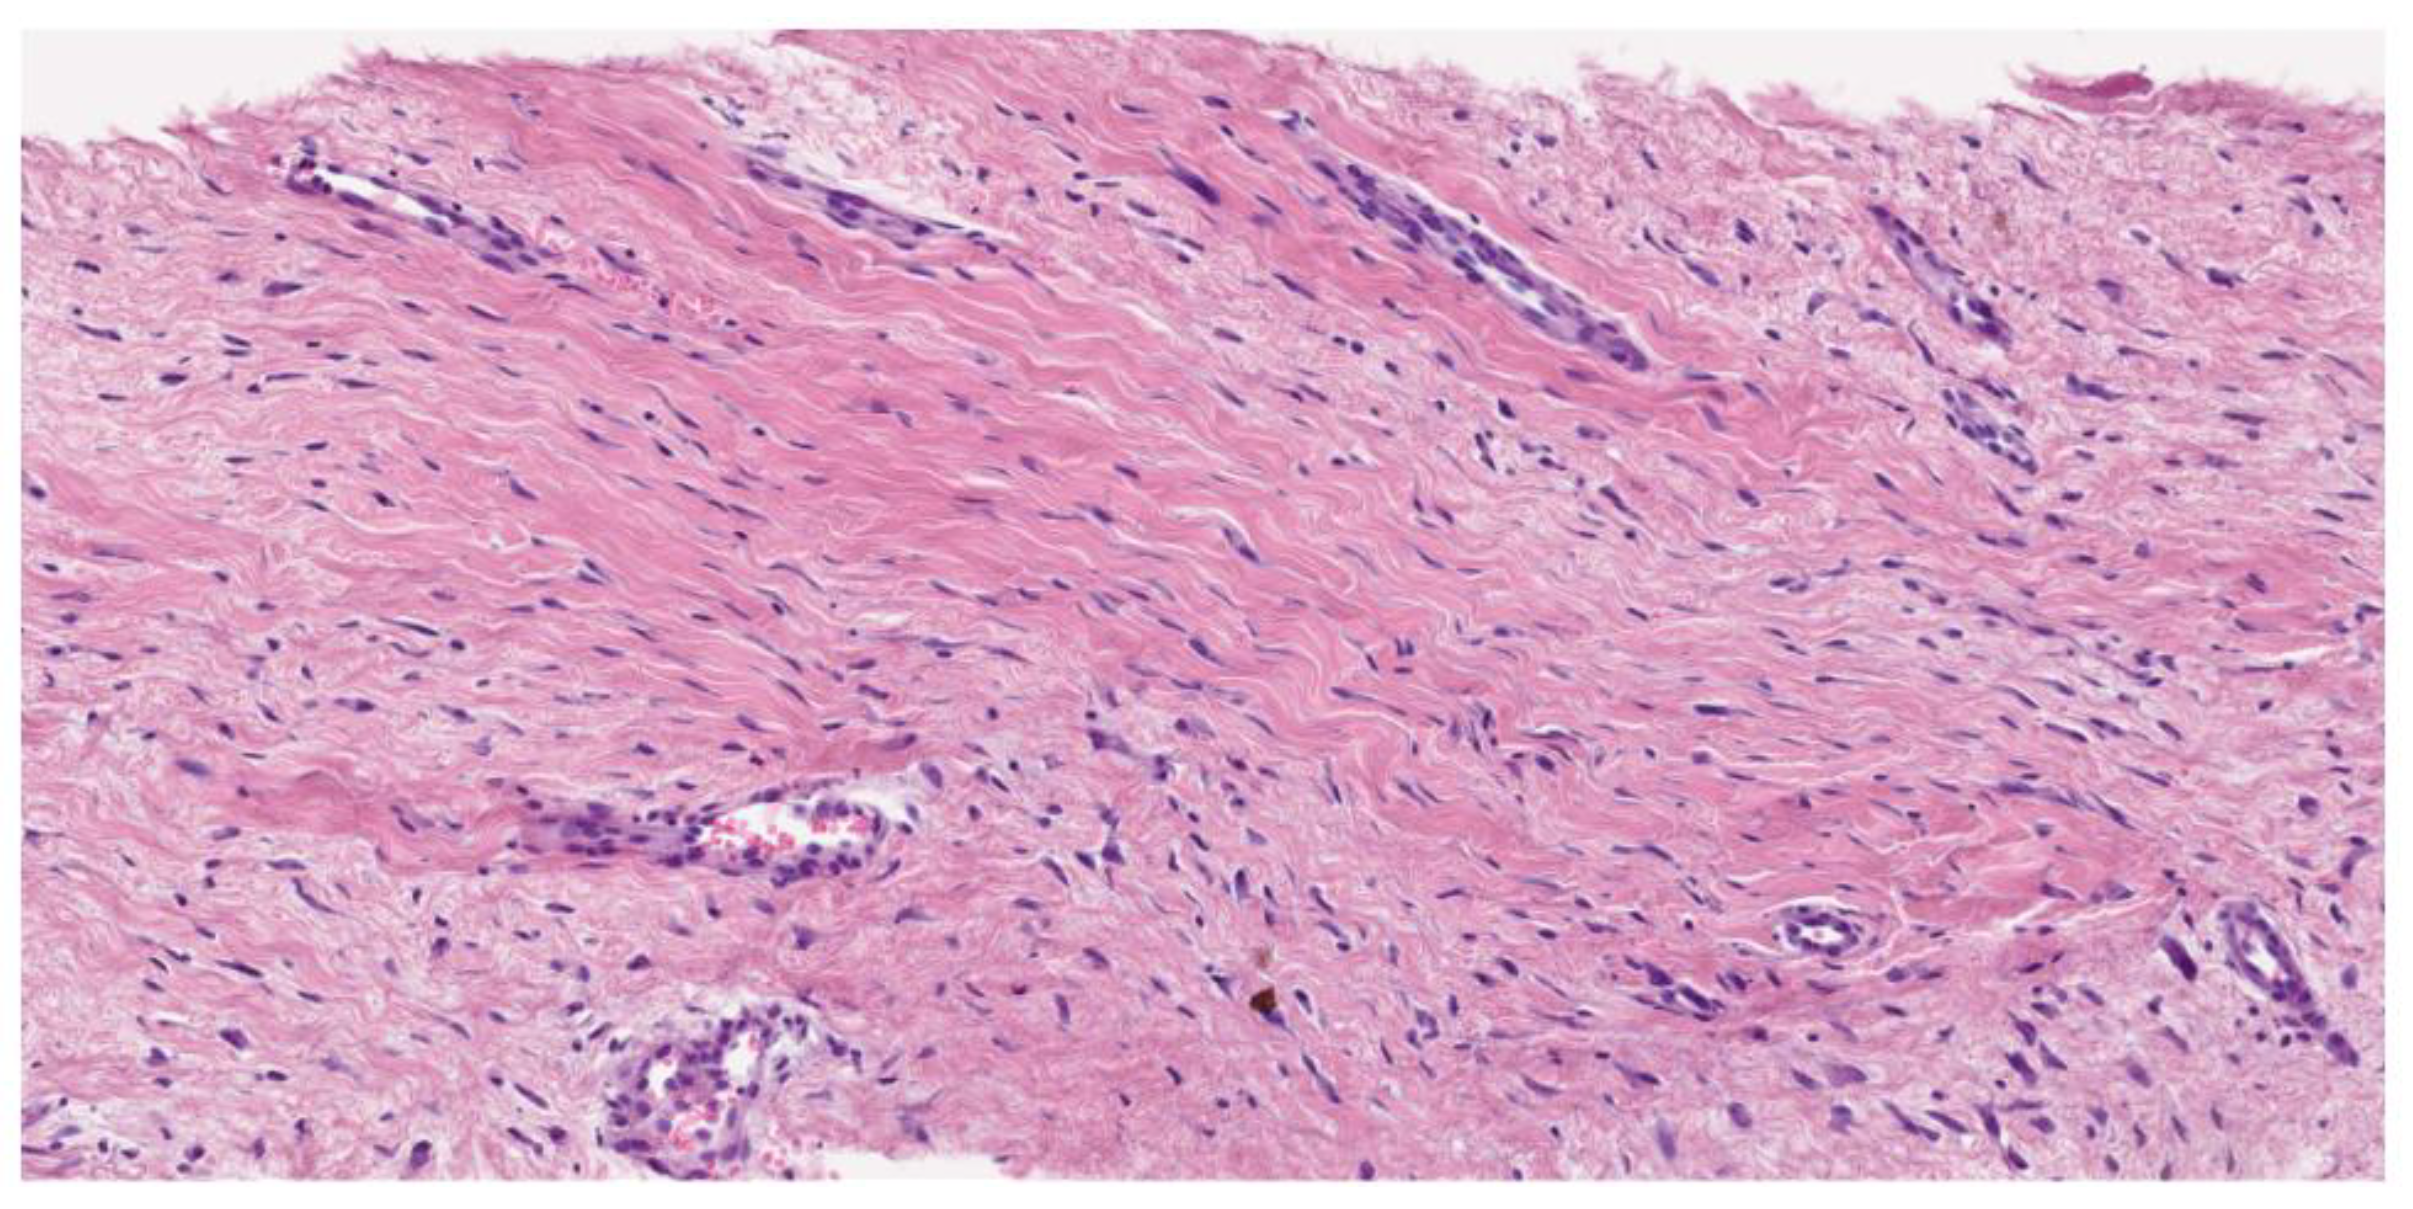

Desmoid fibromatosis is a low-grade, isomorphic spindle cell neoplasm composed of bland fibroblasts and myofibroblasts with infiltrative borders, arranged in long, sweeping fascicles. Characteristically, it features a collagenous stroma (containing rounded, intermediate-caliber vessels with subtle perivascular edema). The uniform lesional cells display a pale eosinophilic cytoplasm, tapering nuclei, fine chromatin (with no nuclear hyperchromasia or atypia), and rare or absent mitotic activity. Atypical mitosis is not observed. In addition to this conventional pattern, some examples can be hyalinized/hypocellular, myxoid, keloidal (a finding most common in intra-abdominal tumors), nodular fasciitis-like (especially when arising in mesentery), and hypercellular, sometimes with staghorn vessels (Solitary Fibrous Tumor-like vessels). A case with nuclear pleomorphism and TP53 mutation has been described by Foster and coworkers [22].

Figure 2. Hematoxilin–Eosine (16,6X). Long, sweeping fascicles of bland fibroblasts without atypia or hyperchromasia.